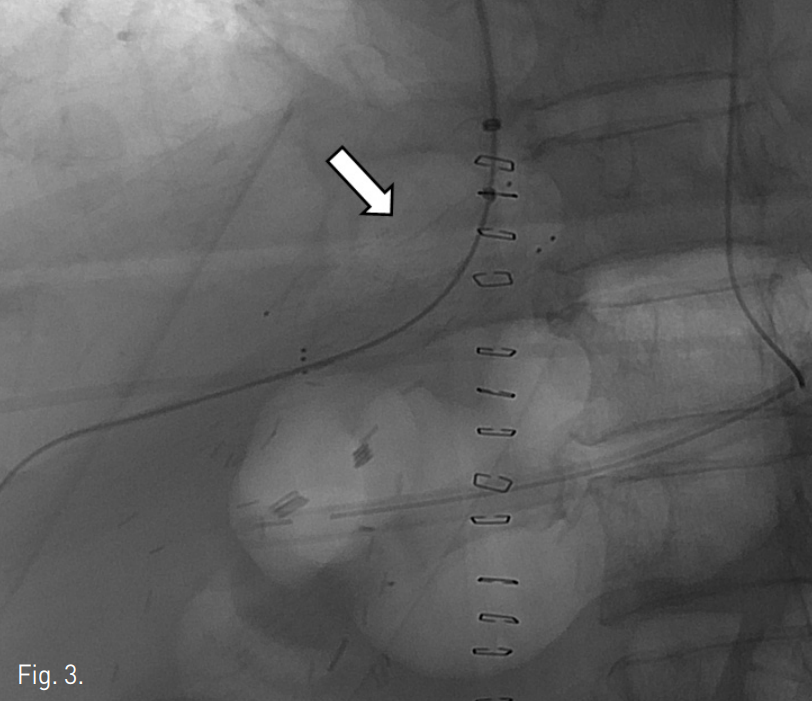

오른손목정맥을 천자한 뒤 6F shuttle sheath (Cook, Bloomington, U.S.A)를 삽입하였다. Cobra catheter (Cook, Bloomington, U.S.A)와 0.035-유도철사 (Terumo, Japan)를 이용해 오른간정맥을 선택한 후 협착된 부위를 사이에 두고 원위부 간정맥과 아래대정맥 간 측정한 pressure gradient는 9~10mmHg였다. 협착된 부위에 14mm x 4cm

Zilver 스텐트 (Cook, Bloomington, U.S.A)를 삽입하였다(Fig. 3). 스텐트 삽입 후 측정한 pressure gradient는 4mmHg로 감소되었으며 정맥조영술에서 협착은 보이지 않았다. 시술 직후 통증이나 활력 징후의 변화와 같은 합병증은 관찰되지 않았다. 시술 다음날 시행한 color doppler 검사에서 오른간정맥의 spectral waveform이 triphasic하게 관찰되었으며 추적 검사에서도 동일한 소견이 관찰되었다. 시술 후 시행한 CT angiography에서 스텐트는 이전 CT에서 보였던 협착된 부위에 삽입되어 있음을 확인하였고, 스텐

Fig. 3

A self expandable metallic stent (arrow) was successfully placed across the anastomotic stenosis.